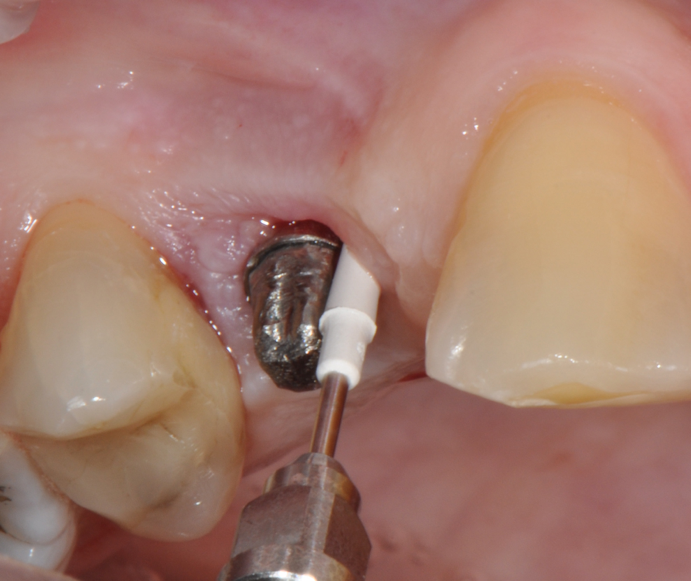

Fig.8: Implant surface debridment with piezo-ceramic device and PEEK tip.

So far, there is no scientific evidence supporting the efficacy of this coadjuvant. The tested protocol consist of a Multiple Anti Infective Non Surgical Therapy (MAINST) that involves the use topical 14% doxycycline to solve the peri-implantitis acute phase and, after 7 days, a session of Full Mouth Air Polishing Therapy (FM-EPAPT) through erythritol powder (Fig.7), a piezo-ceramic device with a PEEK tip (Fig.8), the curettage of internal pocket line (Fig.9) and a second application od Doxy. The patients were further followed with quarterly maintenance sessions carried on with the same FM-EPAPT protocol. Up to 12 months BOP and mean PD decreased significantly and successfully, accompanied by a gain of attachment level up to 12 months. The first case-series about MAINST is waiting to be published and the results are encouraging. Figure 10 and 11 show the healing at 6 and 12 months after MAINST protocol of the peri-implantitis case displayed at the beginning of this article (Fig.1,2,3,4) and figure 12-21 show a complete MAINST case.